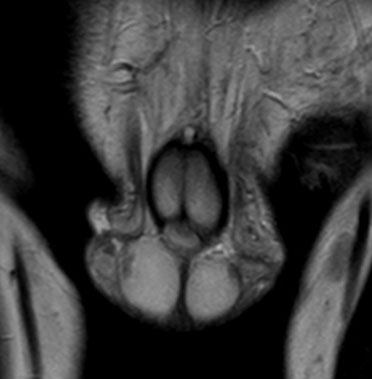

Adrenal rests were noted in both testes; the scrotal ultrasound and MRI showed bilateral eccentric lobulated lesions adjacent to the mediastinum in the testes. No calcification or vascularity was seen in the testicular lesions (Figure 2A, Figure 2B and Figure 3).

Figure 2: Testicular adrenal rests on scrotal ultrasound imaging. (A) Longitudinal ultrasound image of the right testis. (B) Longitudinal ultrasound image of the left testis.

Figure 3: Testicular adrenal rests: MR coronal T2-weighted images showing bilateral eccentric hypointense lesions in the testes.

The hallmark of the SV-CAH is virilization in females and precocious puberty in males along with enhanced somatic growth; all due to androgen hypersecretion. The index patient presented with features of peripheral precocious puberty, secondary sexual characteristics, and advanced bone age with no clinical and biochemical features of SW. The revelation of high testosterone level with low FSH and LH associated with pre-pubertal testes size are indicative of peripheral PP in our case [9]. Congenital adrenal hyperplasia is associated with adrenal abnormalities, namely, adrenal hyperplasia, myelolipoma, benign adenoma, and rarely pheochromocytoma [10]. In patients with CAH, myelolipoma is common in those who were diagnosed late or poorly controlled. Although, no adrenal abnormalities were noted in our patient, follow-up imaging of patients with CAH is important especially in those who present with abdominal pain [11]. Male patients may have ectopic adrenal tissue which may be found anywhere along the gonadal descent pathway [10]. The reported prevalence of testicular adrenal rests in patients with CAH is 24% [12]. Classically, the ectopic adrenal tissue in males may be found in the testes. Likewise, testicular adrenal rests were noted in both testes of the index case.